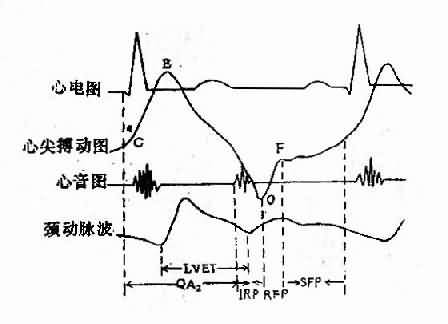

包括心音图、心尖搏动图、颈动脉搏动图及心电图同步记录,在某些病例可协助判定物理检查所见,如心音图可协助确定心音或杂音的发生时期有无附加音,通过杂音的形态可帮助辨别病变的性质。测定收缩时间间期,可判定左心室收缩功能。例如左室喷血时间(LVET)为颈动脉波从开始上升至切迹这一段时期;心脏电机械收缩时间(QA2)即由QRS波开始至第二心音动脉瓣成分的时间,喷血前期时间(PEP)即QA2减去LVET,左室不全时,喷血前期时间延长而左室喷血时间缩短,因此PEP/LVET比值增大。测定收缩时间间期对冠心病、心肌病等病人的左心收缩功能判定有一定帮助。(图3-1-3)

图3-1-3 心动周期内左心室各种时相的测定示意图

QA2;电-机械收缩时间;LVET:左心室喷血时间;IRP:等容舒张期;REP:快速充盈期;

SFP:缓慢充盈期